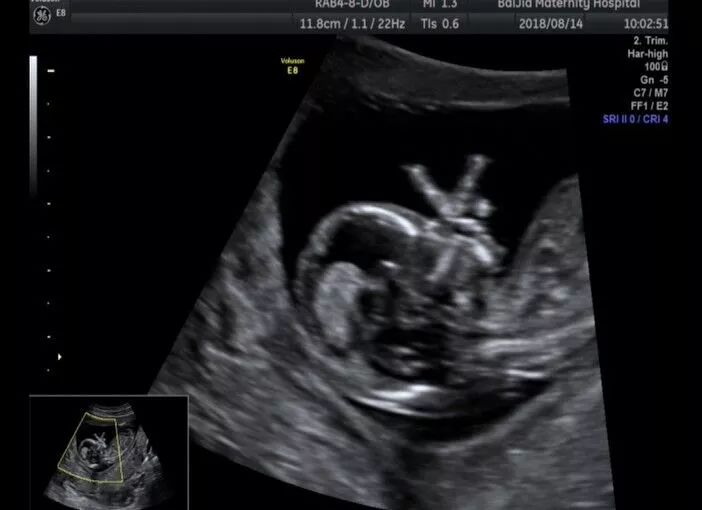

NT检查又称颈后透明带扫描,是通过B超手段测量胎儿颈项部皮下无回声透明层较厚的部位,用于评估胎儿是否有可能患有唐氏综合征的种方法,也普遍被认为和染色体异常有关。

NT检查能检测胎儿的生长发育情况、胎盘环境、子宫状况等。

NT检查超声探头下捕捉到的

宫内宝宝欢乐场景

你们想遇见这样的宝宝吗?